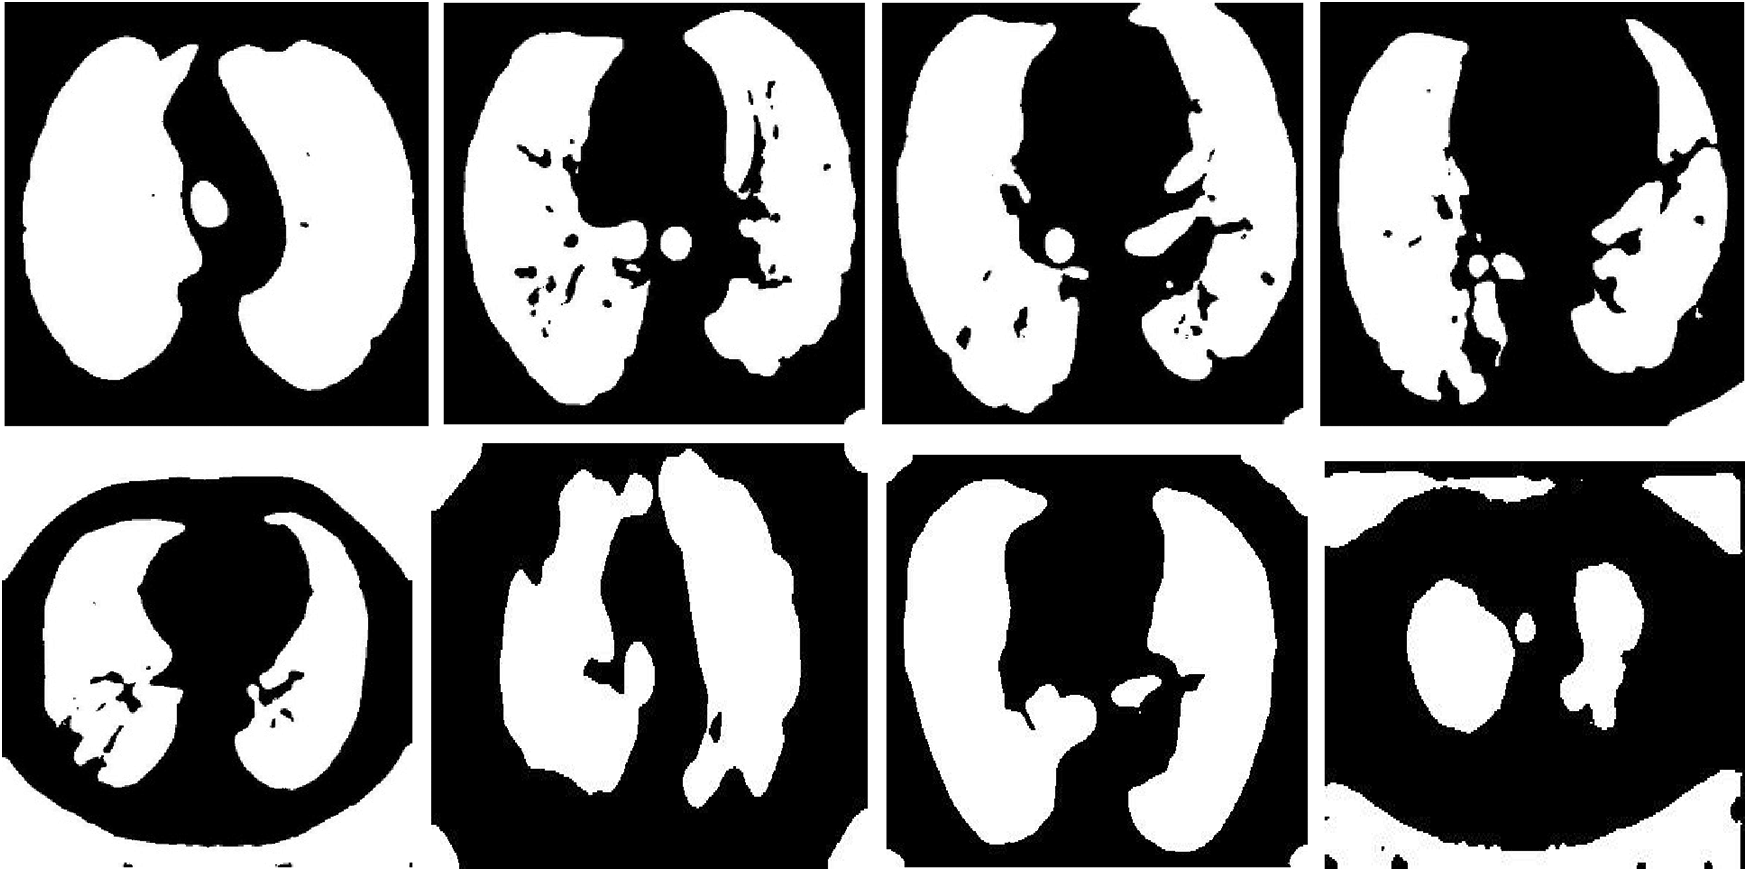

Fig. 12 shows samples of the resulting segmented COVID-19 CT images. Fig. 13 shows samples of the resulting segmented pneumonia CT images. Tab. 4 shows evaluation metric values for samples of the resulting segmented COVID-19 CT images. Tab. 5 gives evaluation metric values for samples of the resulting segmented pneumonia CT images. Tab. 6 shows a comparison of the suggested framework for segmentation with other models. Tab. 7 shows a comparison of the suggested framework for classification with other models.

Figs. 12 and 13 illustrate the resulting segmented COVID-19 and pneumonia CT images. The visual images reveal the difference between COVID-19 and pneumonia cases in segmented images. In addition, the evaluation metrics of the resulting segmented images ensure high accuracy and efficiency of segmentation.

Figure 12: Samples of resulting segmented COVID-19 images

Figure 13: Samples of resulting segmented pneumonia images